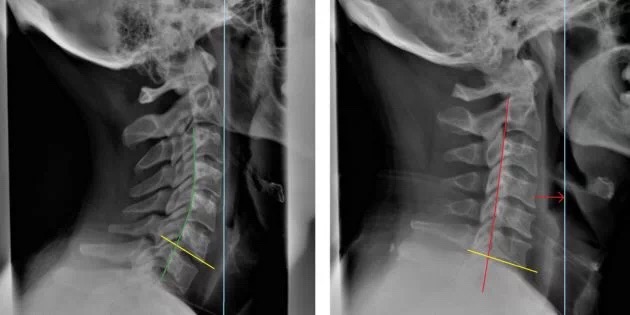

关于头前伸的危害,除了从美观上我们常常考虑的体态的问题,头前伸最主要的一个危害就是他直接与颈椎病相关联。在颈椎病的病例报告中通常都有这样一个诊断——颈椎生理曲度变直。生理曲度变直其实就是颈椎对头前伸姿势长期适应的结果。

在整体的评估下,侧面观的乳突、肩峰,还有股骨大转子、股骨外上髁、外踝应该是练成一条直线的,这条直线我们称为中线。我们可以用乳突与肩峰的连线与中线的夹角来量化头前伸的角度,也可以用乳突偏移中线的程度来直观感受头前伸的程度。还有一个很简单可行的方法就是靠墙站立,后脑勺是否能很轻松自然地贴到墙面。

首先摆正耳垂,让两个耳垂水平(如红色的线),观察双肩的高度差,如果出现了双肩高度不一致的情况就要注意了,这就是我们常说的高低肩。那么高低肩人群应该拉伸哪一侧肌肉呢?现在从图中可以很清楚的看出,肩膀低的一侧肌肉被拉长,虽然平时你会觉得这一侧肌肉比较紧张,但是真的不能拉伸啊!反而要拉伸肩膀高的一侧,否则高低肩的情况会越来越严重!